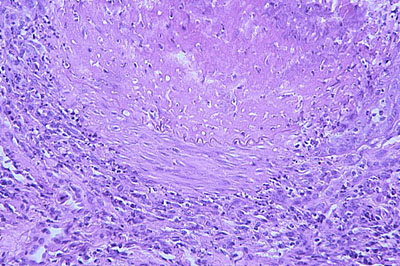

Photo 6 (Hémalun-Eosine – X100) : plus en profondeur,

sous l’ulcère épidermique, on retrouve des silhouettes vasculaires

artériolaires à paroi musculaire épaisse, irrégulière et inflammatoire.

Légendes de la Photo 6 :

- Étoiles turquoises : lumière des vaisseaux sanguins artériolaires.

- Étoiles rouges : infiltrat inflammatoire à prédominance de cellules lympho-plasmocytaires au pourtour des vaisseaux sanguins.